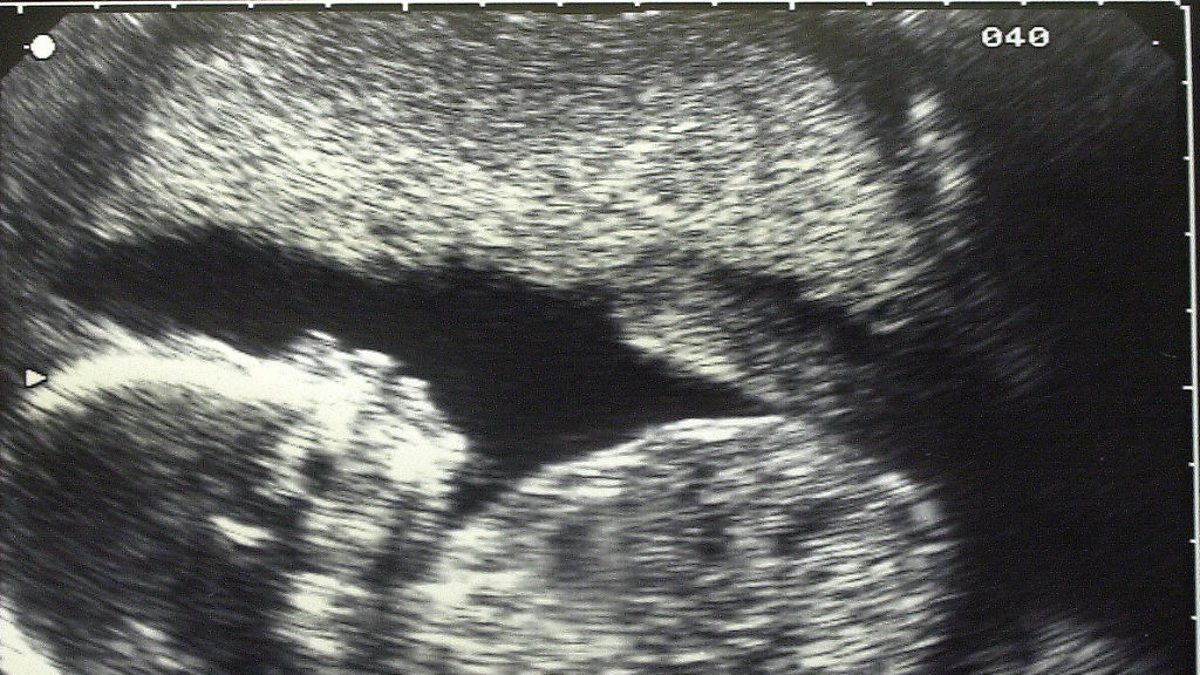

Mercy and Kirsteen share a very special moment with Laura, hearing her baby's heartbeat for the first time and discuss what it was like for them.